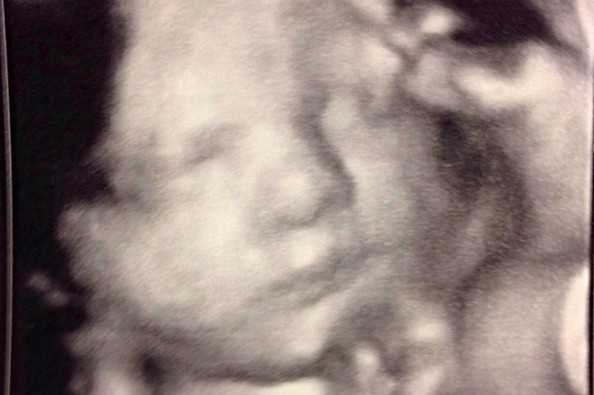

This page is to help raise funds to help with medical bills for pay Tara and DJ Strickland's little boy, Dade. Dade (due to arrive August 12!) was diagnosed with a birth defect known as Congenital Diaphragmatic Hernia (CDH). CDH happens when the diaphragm doesn't form completely and leaves an opening for organs to migrate around the abdominal and chest cavity. Any or all of the stomach, intestines, and liver can migrate into the chest cavity. This is a problem because these extra organs in the chest cavity crowd the heart and lungs, hampering their development. Babies have enough trouble with lung development even under normal circumstances, so CDH only complicates the situation that much more.